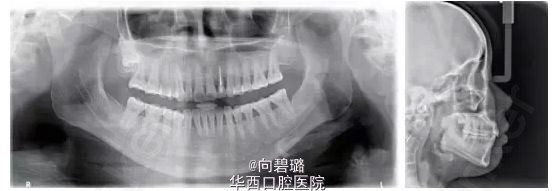

患者为25岁女性,主诉为嘴突,牙稀有缝。 临床检查:口外:颌面部双侧基本对称,侧貌突;中度开唇露齿;口内:双侧磨牙关系基本中性,前牙覆牙合Ⅰ°,覆盖2mm,上下颌牙列各有散隙6mm,口腔卫生差,下颌前牙牙龈退缩(GR):4mm,31、41松动Ⅰ°~Ⅱ°。 影像学检查:X线片示全口牙槽骨中到重度水平吸收;22牙牙根周圆形低密度影像;上前牙牙根圆钝;18牙高位阻生似有囊液,38牙近中倾斜。 诊断:安氏Ⅰ类,骨性Ⅰ类,慢性牙周炎,22牙根尖周炎。   矫治目标 关闭上下散隙;协调前牙冠根比;改善侧貌;建立良好前牙覆覆盖。   矫治设计 ①口腔健康宣教,牙周牙体系统治疗后评估牙周情况,稳定后开始正畸治疗;②不拔牙矫治,使用隐适美(Invislign)矫治技术配合片切。 总结: 牙周炎进展过程中的牙槽骨吸收,造成了前牙的病理性移位,形成创伤进一步加剧牙周组织丧失。可摘戴的矫治器(aligner)对牙齿作用为间断轻力、菌斑控制更方便有效;合理的正畸设计去除前牙创伤、协调前牙冠根比,这均有利于牙槽骨的积极改建。悄然蝶变,患者牙突、嘴突情况解决,对治疗过程、疗效均十分满意。